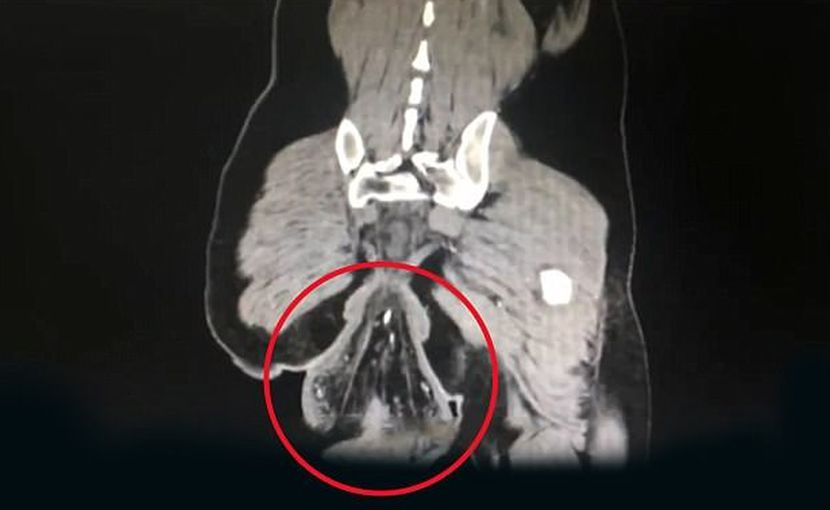

Gambar imbasan CT pesakit lelaki terbabit.

"Hasil imbasan CT menunjukkan bonjolan berbentuk bola tenis di luar dubur pesakit mempunyai diameter sekitar 16 sentimeter," jelas laporan hospital tersebut.